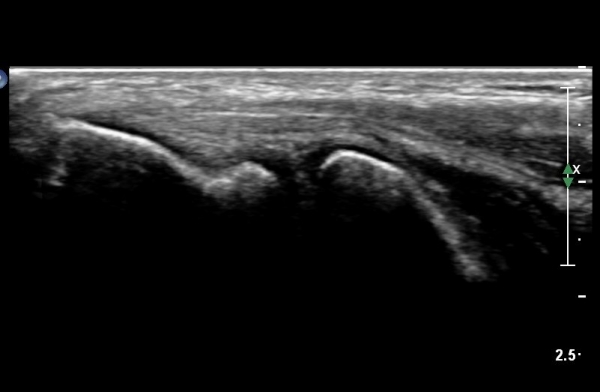

³»»ó°ú¿Í ±¼°î°Ç Á¾´Ü¸é°Ë»ç¿¡¼­ ƯÀÌ ¼Ò°ß º¸ÀÌÁö ¾ÊÀ½(»çÁø2).

¼ÒµÎ Á¾´Ü¸é°Ë»ç¿¡¼­ ¼ÒµÎ¿Í ¿ä°ñµÎ Àü¹æ¿¡ ¼ö¾×Àú·ù°¡ °üÂûµÊ(»çÁø 3, 4).